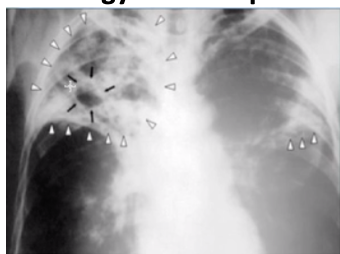

Miliary TB